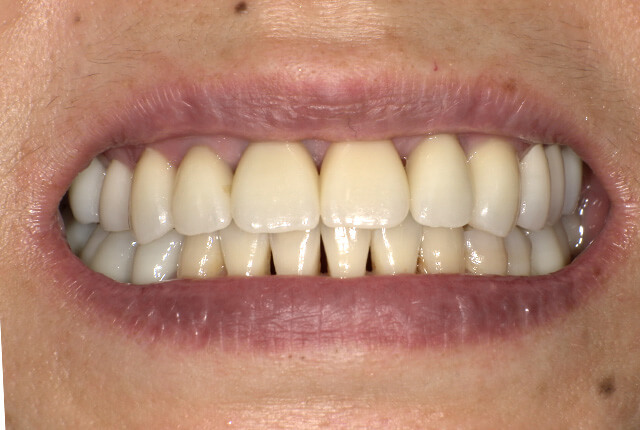

| 主訴 | 噛めない、食事がしっかりできる様になりたい。 |

| 診査診断 | 歯周病、歯の崩壊、不良補綴。 全顎的咬合異常、前歯の噛み合わせ、奥歯の噛み合わせに問題あり。 |

| 治療計画 | 欠損部インプラント 不良補綴のやり直しと欠損部インプラント。 咬合の再構築、なるべく歯を残せる様に治療計画を立案。 |

| 治療期間 | 6ヶ月 |

| 費用 | 290万円 |